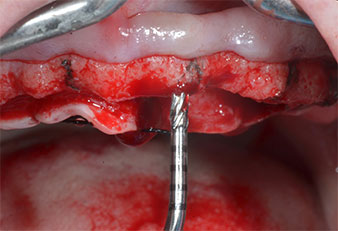

Moteur d'implantologie (Implantmed)

Fig. 5 : Le diamètre définitif est obtenu à l'aide des inserts Piezomed I3A/I3P. Pour les implants de 10mm aux régions 11 et 21, les sites sont finalisés à l'aide d’une fraise de 3,5mm dans un moteur d'implantologie (Implantmed).